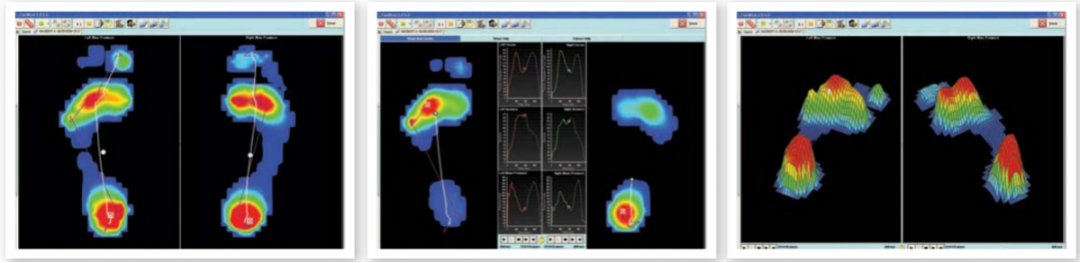

平板式足底压力分布采集分析系统

美国SPI平板式足底压力分布采集分析系统从遍布传感器板的数千个微小的压电电阻元件中捕捉足部压力变化。就像站在秤上一样,传感器板记录了现场压力和压力的临界分布模式。

可以用于静态、动态足底状况和身体平衡能力的分析,被广泛应用于运动生物力学研究、运动鞋设计、步态分析、平衡分析,糖尿病足的测试、下肢骨关节疾病等临床及科研领域。

Tekscan步道式足底压力分布测试系统

Tekscan步道式足底压力分布测试系统是一套真正模块化的人体步态分析量测步道,超薄的平板可以减少跌倒的风险与步态干扰。

步态数据会以多种方式显示,包括:曲线图、压强分布图形、表格以及图表,以便能快速的识别不对称性、异常与**结果,另外透过数据库,可以协助追踪**成效与比较各时期档案。

便携式的步道,行走一趟可采集多个足迹,非常适合孩童、老人、使用拐杖或步态功能有障碍者。自动侦测、标签并分区,让您能够快速的进行步态分析。